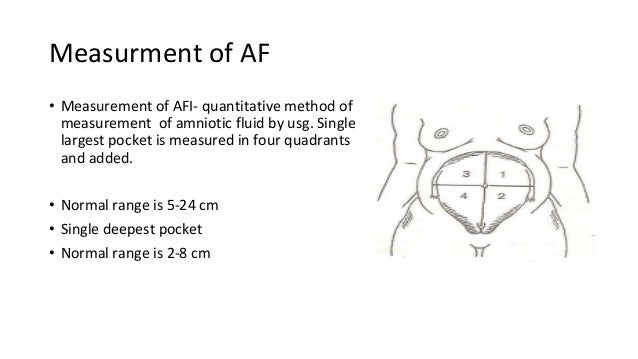

The AFV undergoes characteristic changes with gestation. Pharmaceutical drugs are sometimes prescribed to treat polyhydramnios, such as indomethacin, but concerns have been raised over implications to the unborn baby and other side-effects.Physiology Change in volume through gestation If a fetal bladder obstruction is the cause of oligohydramnios, a small tube can be placed in the bladder to allow the fluid to flow into the amniotic sac. If the cause of the condition is known, then other treatmentsmay be applied. If needed, this option can be done more than once. The opposite is done in treatment of polyhydramnios, where a syringe is inserted into the amniotic sac to drain excess fluid. In some cases of oligohydramnios, extra fluid has been added to the mother's amniotic sac in an effort to increase amniotic fluid levels within the uterus. The amniotic fluid index chart shows the average volume of amniotic fluid in a pregnant woman based on gestational agein millimeter. There areseveral approachesto test the most commonly used methods are the four-quadrant techniqueand the 'single deepest pocket'. Unfortunately, effective treatments for polyhydramnios and oligohydramnios are limited. The amniotic fluid index (or AFI) is used to estimate the well-being of the fetus by doing an ultrasound of the uterus to estimate the levels of amniotic fluid levels in the uterus. Possible Treatments for Polyhydramnios and Oligohydramnios Polyhydramnios can also lead to certain congenital complications, including Down’s syndrome. Polyhydramnios can lead to many of the same complications as oligohydramnios, and the extra fluid can leak through the vagina in rare instances. The symptoms of polyhydramnios for this include edema, difficulty breathing, and excessive weight gain. There are often no symptoms experienced by the mother, except for their belly not growing in alignment with their duration of pregnancy, being smaller than it should. Having low levels of amniotic fluid inside the uterus during pregnancy can lead to numerous problems, which include miscarriage, premature birth, and stillbirth. With the amniotic fluid index chart above, you will wander what are the possible complications along with oligohydramnios and polyhydramnios? Low Amniotic Fluid Levels If there are high amounts of amniotic levels in a mother's uterus then it is known as polyhydramnios, whereas having small amounts of amniotic fluid can lead to oligohydramnios. What If I Have Abnormal Amniotic Fluid Levels? With the pregnancy process going on, the AFI values are changing, and the percentile for fetus age is usually referred as the cutoff value. The AFI 250mm is assumed as polyhydramnios. After 35 week, AFI levels usually begin to reduce. An average AFI level is 80 mm to 140 mm when you are in your 20 weeks to 35 weeks of pregnancy. Usually, the normal value of amniotic fluid index varies from 50 mm to 250 mm (or 5 cm to 25 cm). The sum of the four quadrants, in millimeters or centimeters, is amniotic fluid index. The deepest pocket without fetal parts or umbilical cord is then measured in millimeters or centimeters vertically. Using the umbilicus and the linea nigra as horizontal and vertical axis, an imaginary divide is created inside the uterus, which is split into four quadrants. Techniques and Values of Amniotic Fluid Index Charts Technique The amniotic fluid index chart shows the average volume of amniotic fluid in a pregnant woman based on gestational agein millimeter.Īmniotic Fluid Index Chart Percentile Values

The amniotic fluid index (or AFI) is used to estimate the well-being of the fetus by doing an ultrasound of the uterus to estimate the levels of amniotic fluid levels in the uterus. Assessing amniotic fluid determines an important dimension of fetal health.